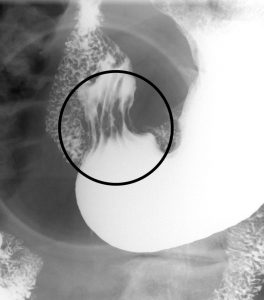

横胃なので病変部位が分かりにくいが、立位圧迫撮影により前庭部後壁にあることがわかる。このような横胃では振り分けが難しい場合、形態がわかるような撮影を試みなければならない。

圧迫撮影から陥凹を呈していることがわかる。陥凹の形状は不整形、陥凹の境界は棘状を示している。ヒダは正常に見える。これにより悪性の可能性が高いことが分かり、精密検査にまわすことが望ましい。

次に内視鏡画像を提示する。

生検の結果 分化型 pap が検出された。